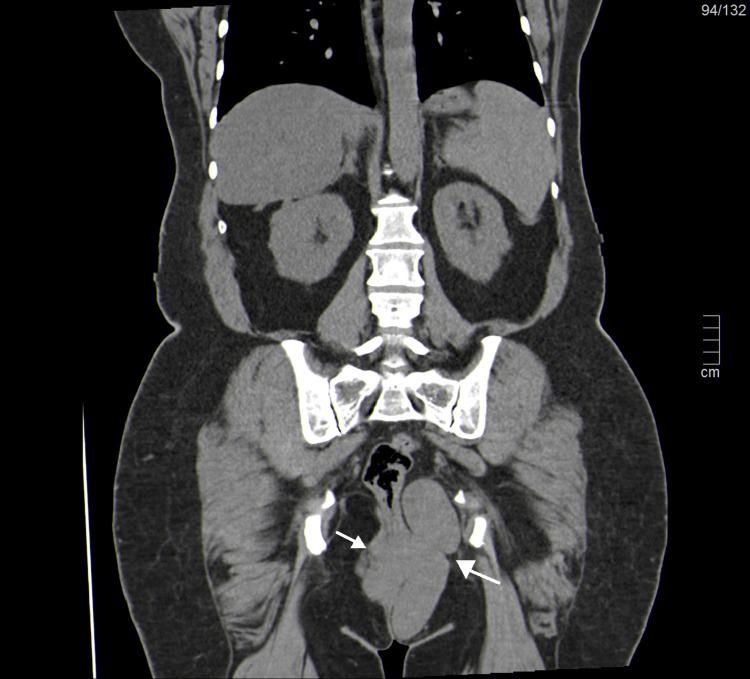

Vulvar leiomyomas are extremely rare smooth muscle tumors that are easily mistaken for other lesions, as the differential diagnosis must consider a wide spectrum of benign and malignant lesions. We present the case of a 52-year-old woman with a three-year history of progressive abdominal distension and pain and an enlarging vulvar mass distorting the labia majora and causing gait disturbance. Imaging confirmed an enormous pelvic mass originating in the uterus, compatible with a leiomyoma/sarcoma, and large perineal and vulvar masses with similar characteristics. Histopathology after surgical removal revealed benign abdominal, vulvar, and perineal leiomyomas. This case highlights the rarity and diagnostic challenges of extra-uterine leiomyomas, particularly those in the vulvar region.

外阴平滑肌瘤是极为罕见的平滑肌肿瘤,很容易被误诊为其他病变,因为鉴别诊断必须考虑多种良性和恶性病变。我们报告一例52岁女性病例,该患者有三年进行性腹胀和腹痛病史,外阴肿物不断增大,使大阴唇变形并导致步态障碍。影像学检查证实盆腔有一个巨大肿物起源于子宫,符合平滑肌瘤/肉瘤表现,同时还有具有相似特征的会阴和外阴大肿物。手术切除后的组织病理学检查显示为良性的腹部、外阴和会阴平滑肌瘤。该病例突出了子宫外平滑肌瘤的罕见性及诊断挑战,尤其是外阴区域的平滑肌瘤。